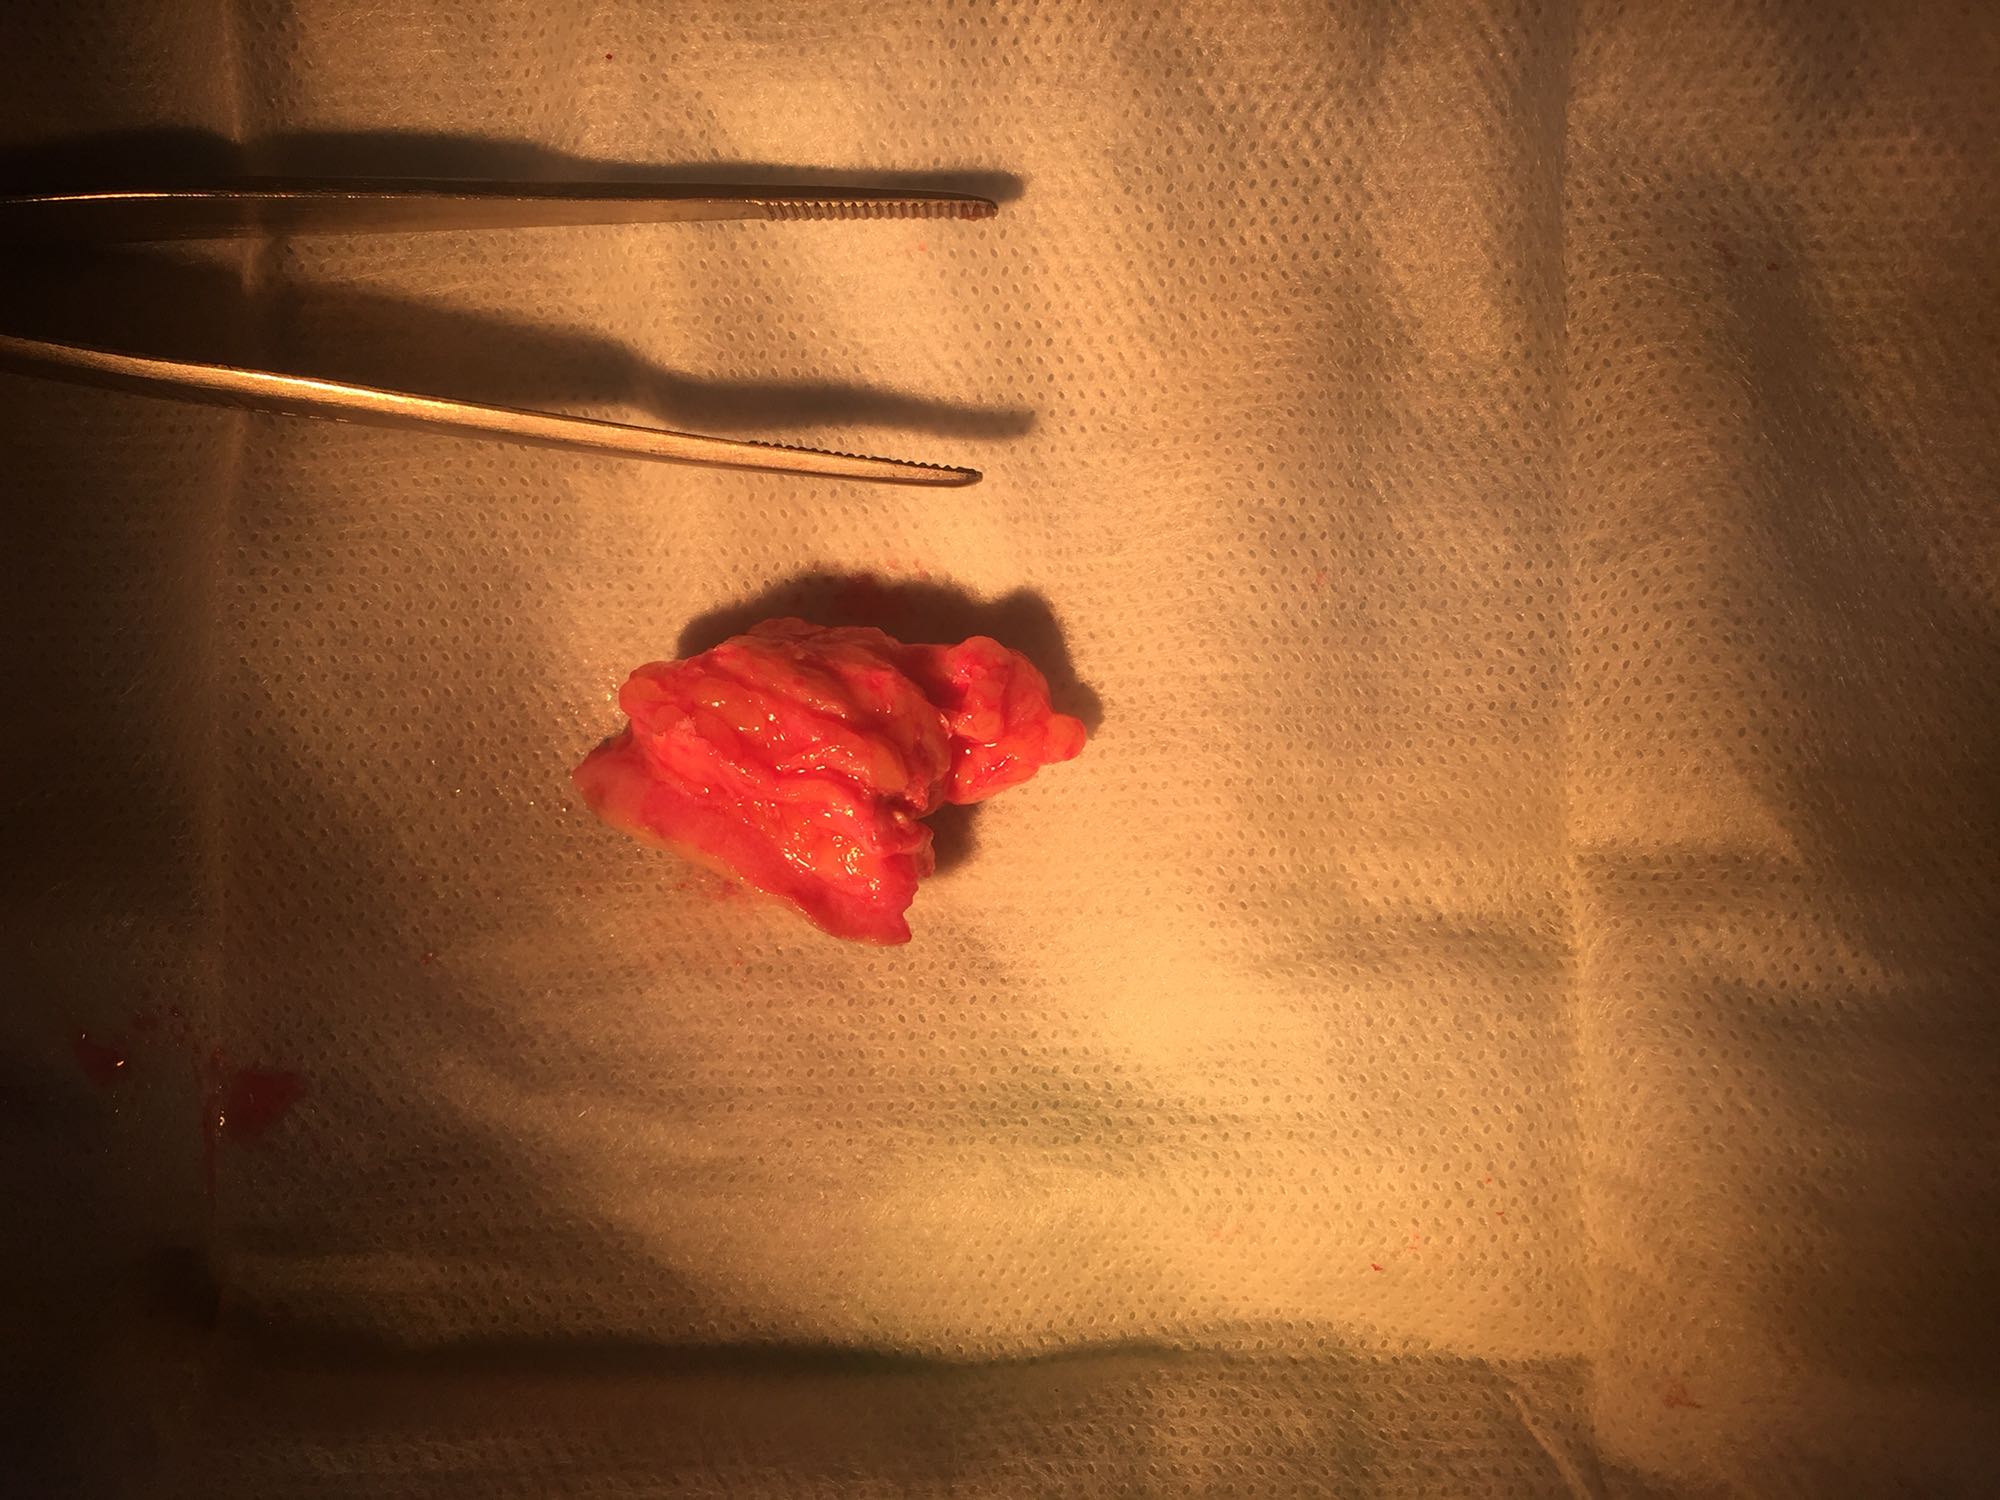

诊断:左侧大腿皮下肿物。 治疗:局麻下行左侧大腿皮下肿物切除手术,术中见肿物不规则,约4*3*3cm大小,质地不均匀,内有多个骨骼样肿物,无包膜。术后病理:钙盐沉积伴慢性炎症。